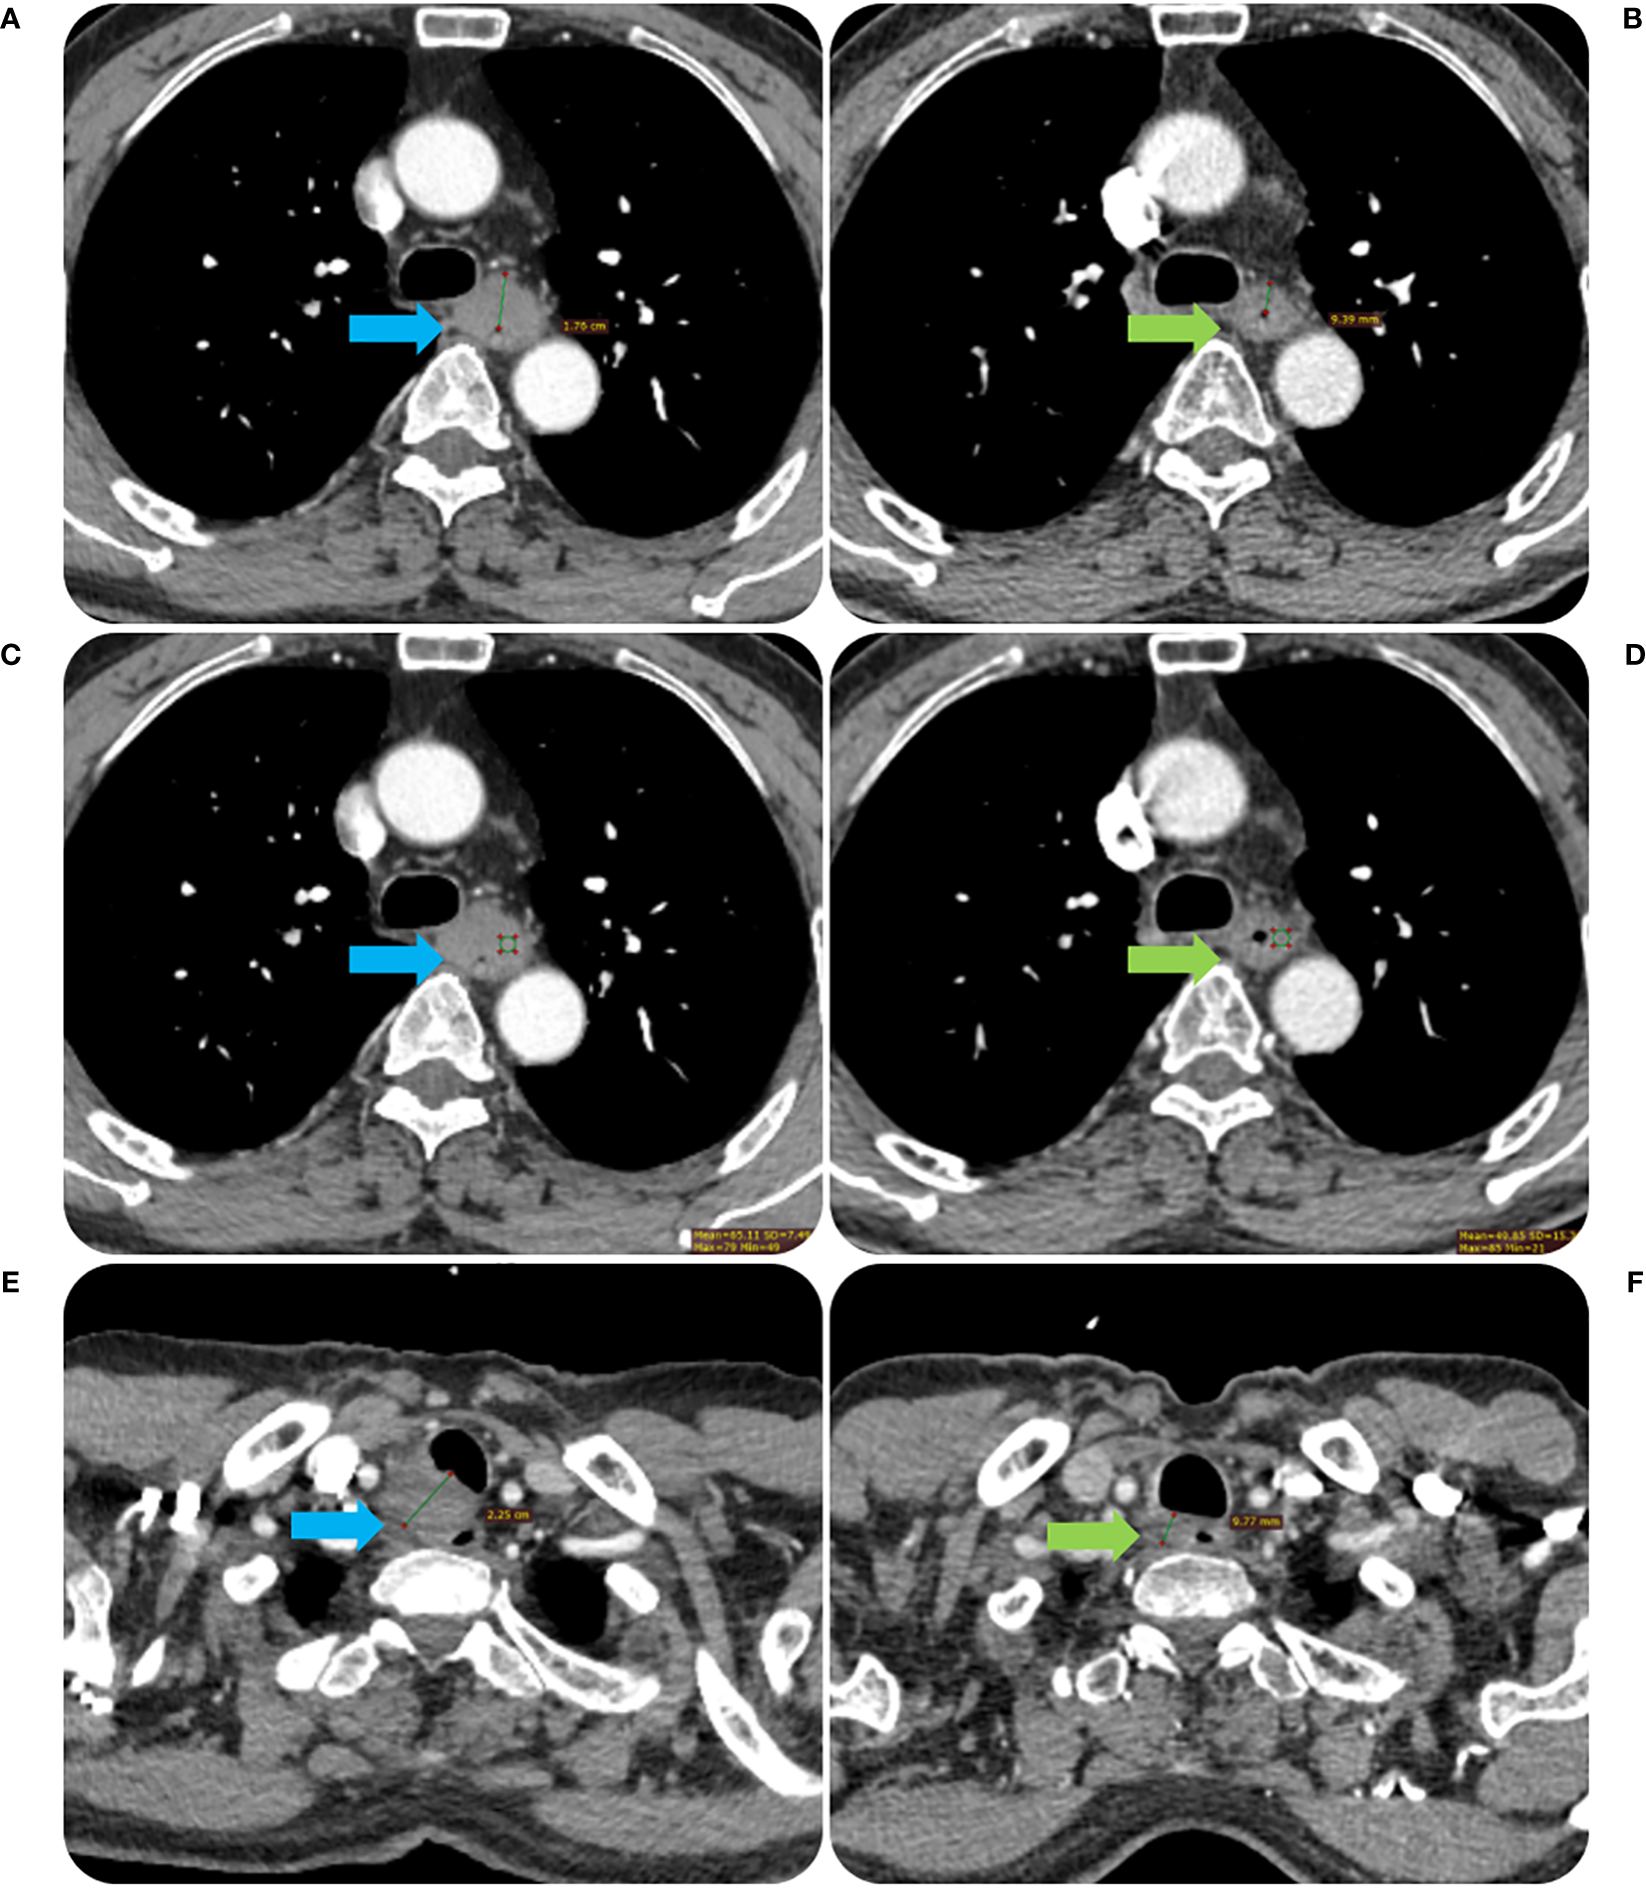

Figure 3

The contrast-enhanced CT images before and after RT of the same patient in Figure 2. The tumor MWT was 1.76 cm before RT treatment (A) and decreased to 0.94 cm after treatment (B). The CT value of the tumor was 65.11 Hu before RT treatment (C) and decreased to 48.85 Hu after treatment (D). The short diameter of the metastatic lymph node in the right proper supra tracheoesophageal sulcus was about 2.25 cm before RT treatment (E), which was reduced to 0.98 cm after treatment (F).

The Radiant DICOM viewer (free software; available online at https://www.radiantviewer.com) was used to upload the thin-slice CECT pictures. The entire tumor was displayed to the greatest extent possible in the sagittal plane using the multi-planar reconstruction mode. The short axis of the biggest lymph node observed in CT images was used to calculate node size, and tumor length was computed based on the axis image. The maximal esophageal wall thickness of the tumor and the short axis of the node at the same level in the area in the transverse section were measured in accordance with the position of the tumor and lymph node before RT. In the transverse slice, a credible tumor region of interest (ROI) was identified within the representative thickened esophageal wall. The software on this image processing workstation automatically calculated the tumor attenuation value. The ROIs covered the largest possible portion of the most noticeably increased area. The tumor’s ulceration and necrosis, gas in the lumen of the tumor, blood vessels, and the adipose around the lesions were all avoided as much as possible when drawing the ROIs. Three sequential tiers of measurements were made. ΔCT value was defined as the relative change of tumor attenuation value before and after RT. All the CT images were analyzed by a radiologist and radiotherapist (with 11 and 12 years of experience, respectively), and when their assessments disagreed, agreement was reached after consultation. The detailed measurement process is shown in Figures 2, 3.